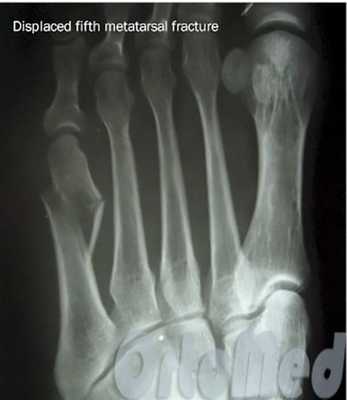

Переломы плюсневых костей

Переломы плюсневых костей по частоте занимают первое место среди всех переломов костей стопы. Обычно возникают при прямом воздействии травмирующей силы (сдавление стопы, падение тяжести или переезд стопы колесом). Могут быть множественными или одиночными. В зависимости от уровня повреждения выделяют переломы головки, шейки и тела плюсневых костей.

При одиночных переломах плюсневых костей выявляется локальный отек на тыле и подошве, боль при опоре и прощупывании. Множественные переломы плюсневых костей сопровождаются выраженным отеком всей стопы, кровоизлияниями, болью при пальпации. Опора затруднена или невозможна из-за боли. Возможна деформация стопы. Диагноз подтверждается данными рентгенографии в 2-х проекциях, а при переломах основания костей плюсны - в 3-х проекциях.

При переломах костей плюсны без смещения накладывают заднюю гипсовую шину сроком на 3-4 недели. При переломах со смещением проводят закрытое вправление, выполняют открытый остеосинтез или накладывают скелетное вытяжение. Срок фиксации при таких переломах костей стопы удлиняется до 6 недель. Затем пациенту накладывают специальную гипсовую повязку «с каблучком», а в последующем рекомендуют использовать ортопедические вкладки.